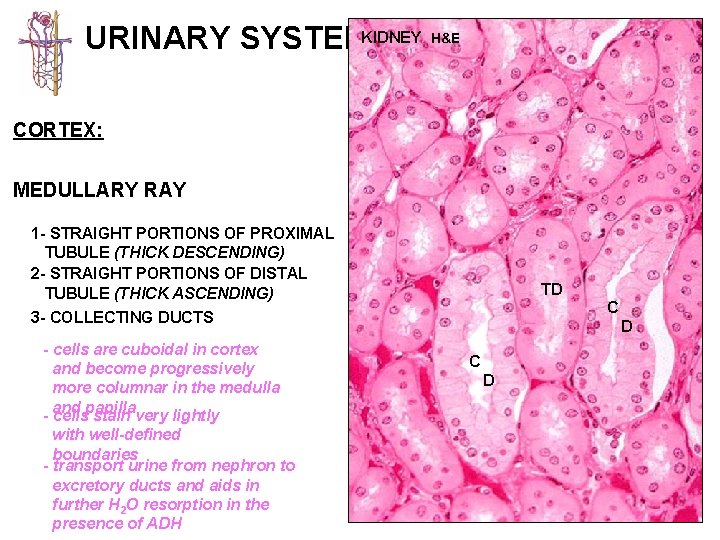

URINARY SYSTEM THE NEPHRON & COLLECTING DUCTS CORTEX: CORTICAL LABYRINTH 1 - RENAL CORPUSCLES 2 - PROXIMAL CONVOLUTED TUBULES 3 - DISTAL CONVOLUTED TUBULES MEDULLARY RAY 1 - STRAIGHT PORTIONS OF PROXIMAL TUBULE (THICK DESCENDING) 2 - STRAIGHT PORTIONS OF DISTAL TUBULE (THICK ASCENDING) 3 - COLLECTING DUCTS

URINARY SYSTEMKIDNEY H&E CORTEX: MEDULLARY RAY 1 - STRAIGHT PORTIONS OF PROXIMAL TUBULE (THICK DESCENDING) 2 - STRAIGHT PORTIONS OF DISTAL TUBULE (THICK ASCENDING) TD C 3 - COLLECTING DUCTS - cells are cuboidal in cortex and become progressively more columnar in the medulla and papilla - cells stain very lightly with well-defined boundaries - transport urine from nephron to excretory ducts and aids in further H 2 O resorption in the presence of ADH D C D